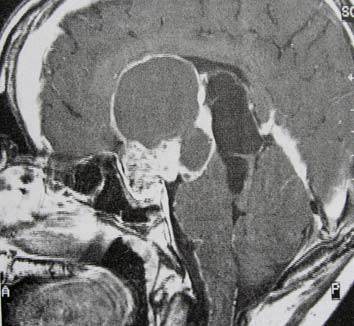

Petunjuk: Seorang laki-laki usia 16 tahun dengan hasil MRI sebagaimana ditunjukkan di bawah ini, dirujuk ke kantor anda. Hasil pemeriksaan laboratorium pasien mengungkapkan bahwa dia menderita hipotirodisme, kekurangan kortisol dan kadar prolaktin sebesar 69. Keluarganya mengatakan bahwa mereka mencatat adanya berbagai perubahan perilaku dan baru-baru ini mengalami kenaikan berat badan. Mata kirinya tidak bisa melihat dan lapang pandangan temporal mata kanannya terputus.

C. Kraniofaringioma

PERTANYAAN 44 - 45

Petunjuk: Seorang laki-laki usia 16 tahun dengan hasil MRI sebagaimana ditunjukkan di bawah ini, dirujuk ke kantor anda. Hasil pemeriksaan laboratorium pasien mengungkapkan bahwa dia menderita hipotirodisme, kekurangan kortisol dan kadar prolaktin sebesar 69. Keluarganya mengatakan bahwa mereka mencatat

adanya berbagai perubahan perilaku dan baru-baru ini mengalami kenaikan berat badan. Mata kirinya tidak bisa melihat dan lapang pandangan temporal mata kanannya terputus.

B. Efek Stalk